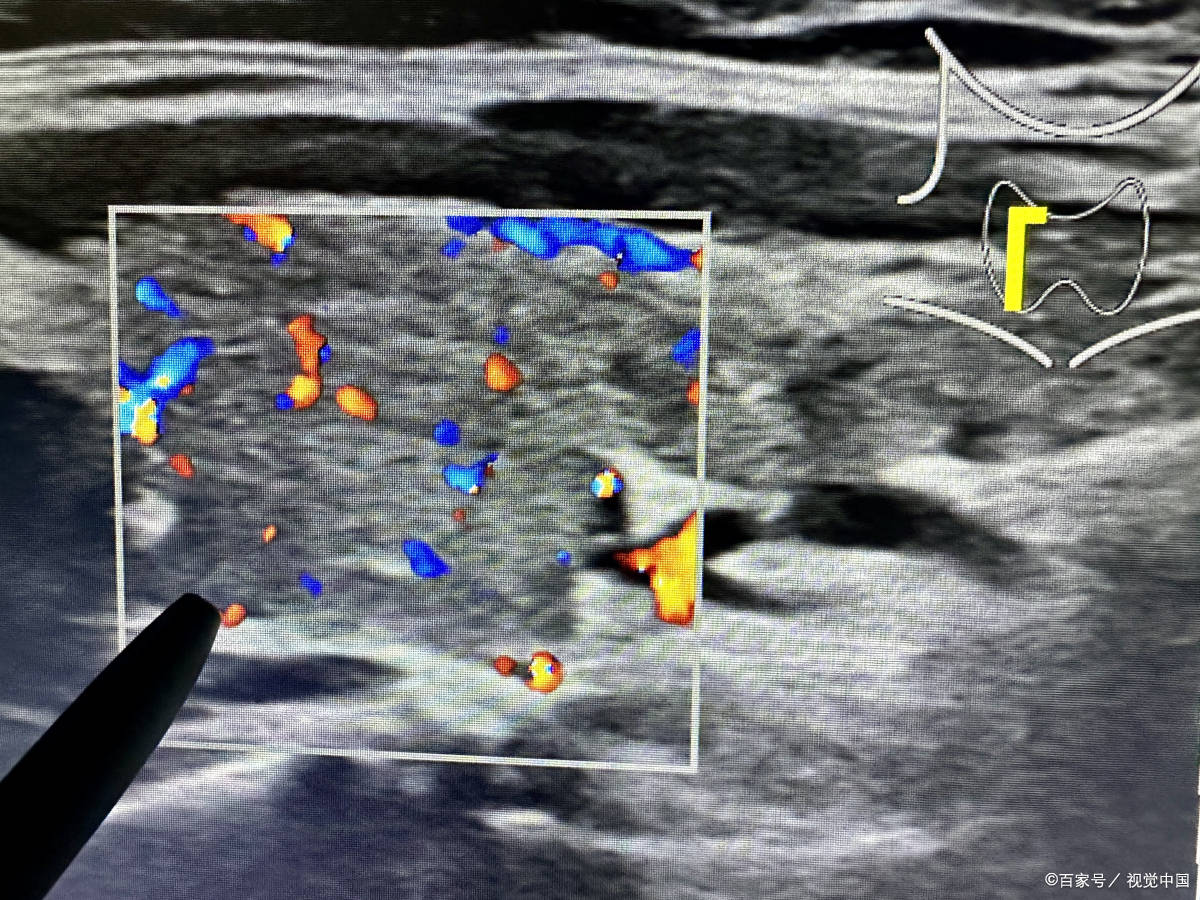

此项技术是新一代国际前沿的消融术,它通过精准的超声引导,能够准确找到病变组织,为结节性病变的治疗提供了全新的解决方案。相比传统的治疗方法,多模态具有微创性、安全性、有效性等特点,为患者提供了更为优质的治疗体验。

使用多模态治疗甲状腺有强阻断、高渗透、恢复快的优势,这种技术能够清晰地呈现病变组织的形态、大小、位置等信息,为医生提供更为精确的手术导航。在手术过程中,医生可以根据这些信息,精确地定位到病变组织,避免对周围正常组织的损伤,从而减少手术风险,提高手术效果。